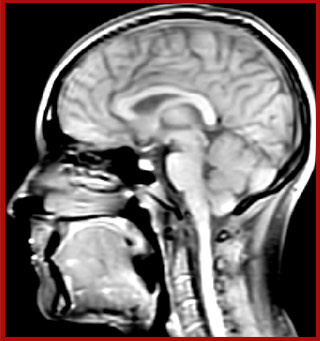

He says the accelerated scanning is achieved via the use of Compressed SENSE and MultiBand SENSE. “We can use Compressed SENSE acceleration factors of about 10 on a 3D FLAIR for instance, which is quite remarkable compared with what we saw with the Achieva. With 3D FLAIR, we can push the spatial resolution to 0.3 cubic mm and it works. Previously, our 3D FLAIR scans lasted about 8 minutes, but now with Elition they are five minutes. The SNR is also visibly better. Our SWI and QSM scans look fantastic. Also, since a lot of neuroimaging is EPI based, using the MultiBand SENSE technique can increase temporal resolution and make it possible to run complicated DTI scans relatively quickly.”

Sagittal 3D FLAIR with 0.3 mm3 voxel volume acquired in 5:12 min. using Compressed SENSE showing a (juxta)cortical MS lesion.